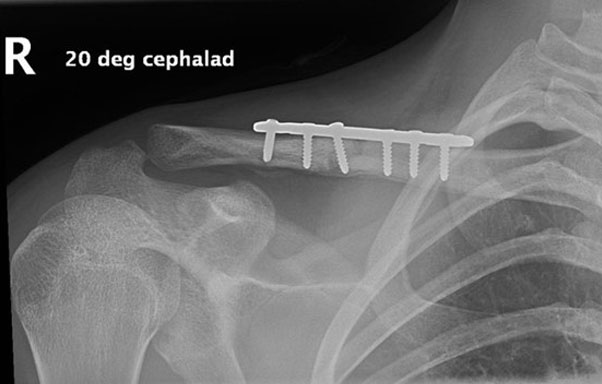

This time he didn’t wait around for treatment overseas, and flew straight back home. He effectively went from the airport to my rooms to the operating theatre that afternoon. This time around I needed to remove the original plate which had held the mid-shaft clavicle aligned while it healed, and replace it with a longer plate which would grab the new fracture fragments at the end of the clavicle (see image below).

Fracture of distal clavicle next to existing plate after fall from mountain bike